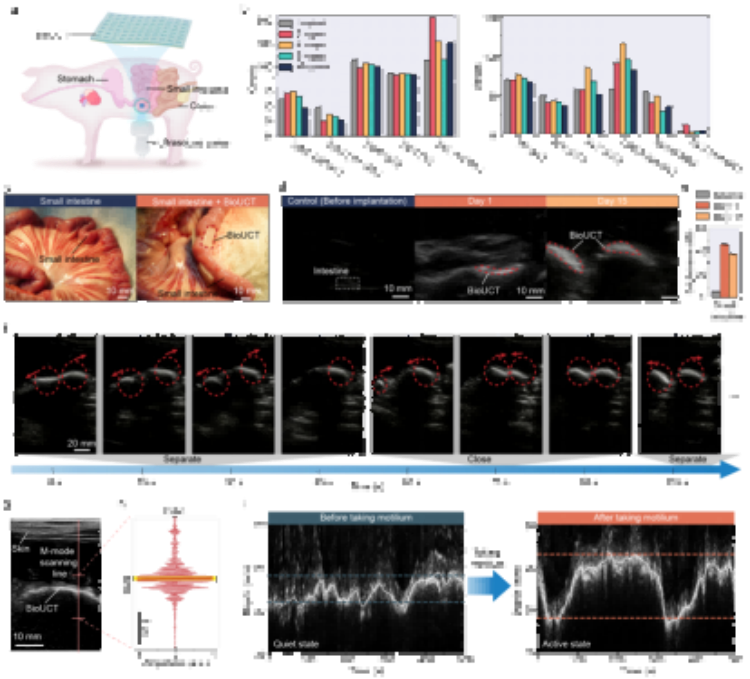

二、應(yīng)用場(chǎng)景

在對(duì)豬腸道蠕動(dòng)幅度監(jiān)測(cè)的驗(yàn)證實(shí)驗(yàn)中,操作人員通過(guò)臨床通用的超聲成像設(shè)備成功追蹤到服藥前后腸蠕動(dòng)幅度的變化(3.13mm→7.59mm)。該技術(shù)未來(lái)可結(jié)合可穿戴超聲設(shè)備,實(shí)現(xiàn)患者居家監(jiān)測(cè),特別適用于:小腸切除術(shù)后并發(fā)癥預(yù)警慢性腸梗阻患者長(zhǎng)期管理胃腸動(dòng)力藥效評(píng)估。

圖5. 通過(guò)BioUCT進(jìn)行活體動(dòng)物腸道運(yùn)動(dòng)監(jiān)測(cè)。